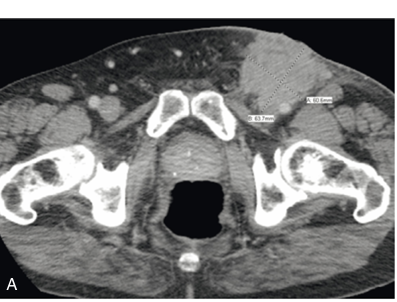

• МРТ або КТ – для виявлення метастазів та планування хірургічного втручання.

• Лімфографія чи біопсія сторожових лімфатичних вузлів – для оцінки ураження лімфатичної системи.